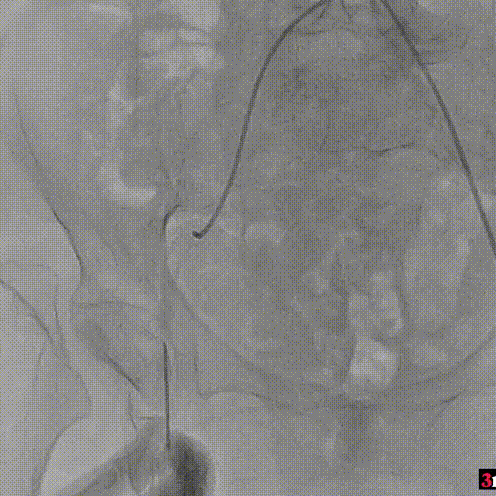

手术过程回顾:

患者全麻后,右侧股动脉建立主入路,主动脉根部造影显示主动脉瓣明显钙化。心室内轻微反流,主动脉及心脏情况整体较为稳定。直头导丝跨瓣后,在超硬导丝支撑下,瓣膜输送系统顺利跨瓣。在180次/分快速心室起搏下,确定降压至50mmHg后选择18mm球囊进行预扩张。在球囊扩张后,该患者血压未见升高,随即进行胸外按压,同时根据术前评估及球囊预扩情况,选取直径23mm瓣膜果断快速进行瓣膜定位并释放。瓣膜释放后患者心律和血压趋于平稳。

主动脉根部造影

直头导丝跨瓣

球囊预扩

瓣膜定位并行胸外按压

瓣膜释放至工作位

瓣膜脱钩

造影查看瓣膜形态

球囊后扩

最终造影

瓣膜释放后,超声提示患者存在一定的跨瓣压差和反流,通过球囊后扩,患者跨瓣压差即刻显著下降,反流量轻微。术后患者心功能持续得到改善,效果良好,此次手术取得圆满成功。